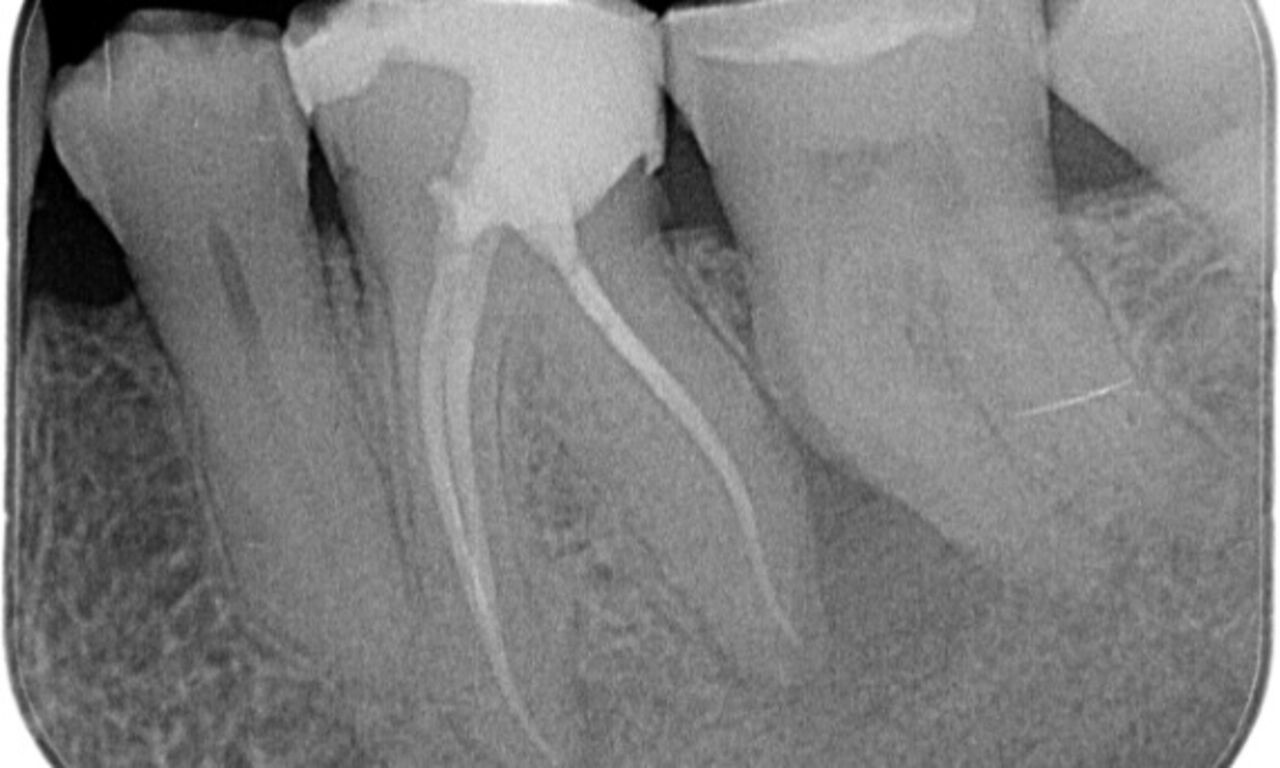

Upon examination, there was a caries lesion related to the lower right first molar. Radiographic examination revealed proximity of the lesion to the pulp horn and combining it with the chief complaint, a final diagnosis of chronic irreversible pulpitis was concluded.

Access cavity was done as conservative as possible. TruNatomy was the system of choice due to the young patient’s age. We needed to preserve dentine as much as possible to increase the tooth ability to overcome occlusal load and increase the longevity of the final restoration.

"I chose TruNatomy to be able to preserve as much dentin as possible to overcome occlusal load and increase the longevity of the tooth."

Dr. Abuelezz